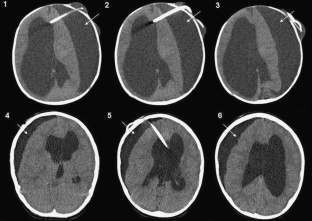

Fig. 1